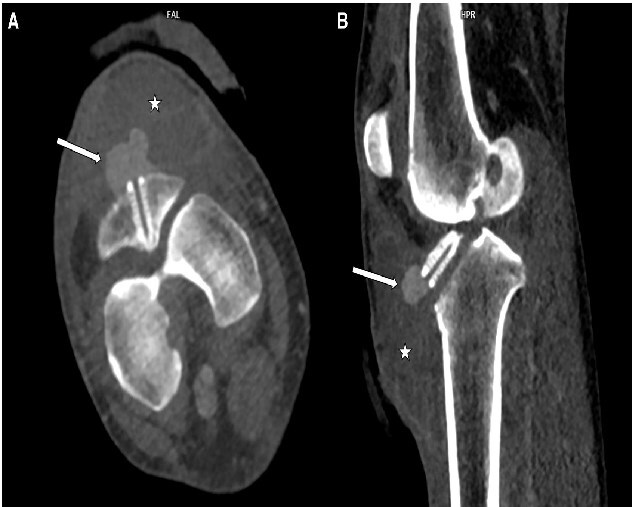

前交叉韧带(ACL)断裂是一种常见的膝关节损伤,通过关节镜重建因其安全性和低并发症发生率(约1%)而广受欢迎。这种手术造成的血管损伤极为罕见,发生率为0.003%-1%。膝关节镜检查后的假性动脉瘤更不常见。本文讨论一例罕见的假性动脉瘤重建后,在右膝内侧间动脉(IMGA)的关节分支,起源于胫骨前动脉高起点。一名47岁的血管性血友病患者在acl重建后30天出现了24毫米的假性动脉瘤。ct血管造影显示假性动脉瘤靠近胫骨隧道螺钉和异常高的胫骨前动脉起源。急诊血管造影证实了这一点,使用Squid Peri 18栓塞成功,无并发症。病人恢复得很好。血管损伤是一种罕见的膝关节镜并发症,但早期诊断和解剖变异的认识是必不可少的。医源性假性动脉瘤的血管内治疗安全有效,且恢复迅速。

Rupture of the anterior cruciate ligament (ACL) is a common knee injury, and reconstruction via arthroscopy is popular for its safety and low complication rate, around 1%. Vascular injuries from this procedure are extremely rare, with an incidence of 0.003%-1%. Pseudoaneurysms following knee arthroscopy are even less frequent. This paper discusses a rare case of pseudoaneurysm after ACL reconstruction in the articular branch of the right inferomedial genicular artery (IMGA), originating from an anterior tibial artery with a high origin. A 47-year-old man with Von Willebrand disease developed a 24 mm pseudoaneurysm 30 days post-ACL reconstruction. CT-angiography showed the pseudoaneurysm near the tibial tunnel screw and an unusually high anterior tibial artery origin. Emergency angiography confirmed this, and embolization using Squid Peri 18 was successful, with no complications. The patient recovered well. Vascular injury is a rare knee arthroscopy complication, but early diagnosis and awareness of anatomical variations are essential. Endovascular treatment for iatrogenic pseudoaneurysms is safe and effective and facilitates rapid recovery.